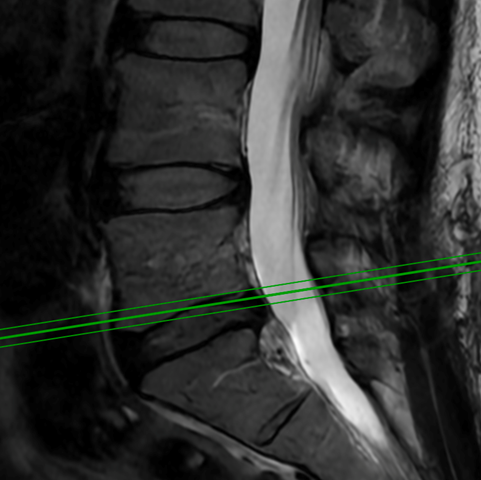

Minimally Invasive Spine Surgery Treats Acute Leg and Foot Weakness